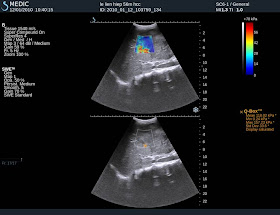

Fig.1A,B: Malignant tumor, Elastic Score=41.76kPa.